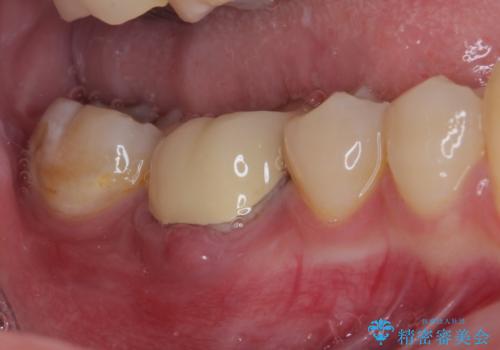

- 奥歯の歯肉から定期的に膿が出てくるとのことで来院された患者様です。

レントゲン写真などの診察を行った結果、根管治療が必要であったため、現在のクラウンを除去し、根管治療を行うこととしました。

根管治療後は症状を確認し、速やかにオールセラミッククラウンにて補綴治療を行うこととしました。